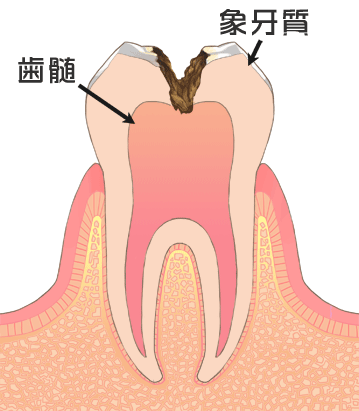

一般的に虫歯(う蝕)とは口腔内に繁殖した細菌が食べ物に含まれる糖質を餌にし、酸を発生させこの酸が歯の表面を溶かし穴が開いていくことをいいます。

エナメル質から象牙質に達し状態です。

痛みはあまりありませんが冷たいものがしみ始めます。

インレー(患部を削ったあとの被せ物)やクラウン(患部を削ったあとの冠状被せ物) などの詰め物、被せ物の治療が必要です。

虫歯部分が歯髄にまで侵食し激しい痛みを伴います。

痛みは一時的なもののため痛みがなくても進行しているケースが多いです。

この場合は、神経の治療が必要になります。

上物はインレー、クラウンなどの治療が必要です。